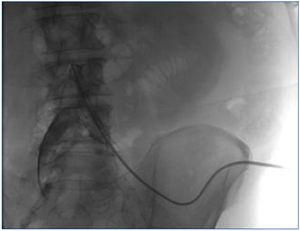

Caso 1. Paciente de 56 años; 4 meses en CAPD sin problemas. Episodio de peritonitis grave por germen anaerobio. Una vez recuperado, inicia tratamiento de APD. Tras unas semanas, acude por imposibilidad para dormir por numerosas alarmas. Se revisa el tratamiento y se comprueba que existe una gran dificultad para drenaje. La radiografía simple de abdomen no muestra hallazgos importantes; se ve la punta en pelvis. Se realiza cateterografía, que muestra gran bucle. Se soluciona pasando una guía y aumentado laxantes (figura 1).

Figura 1. Caso 1